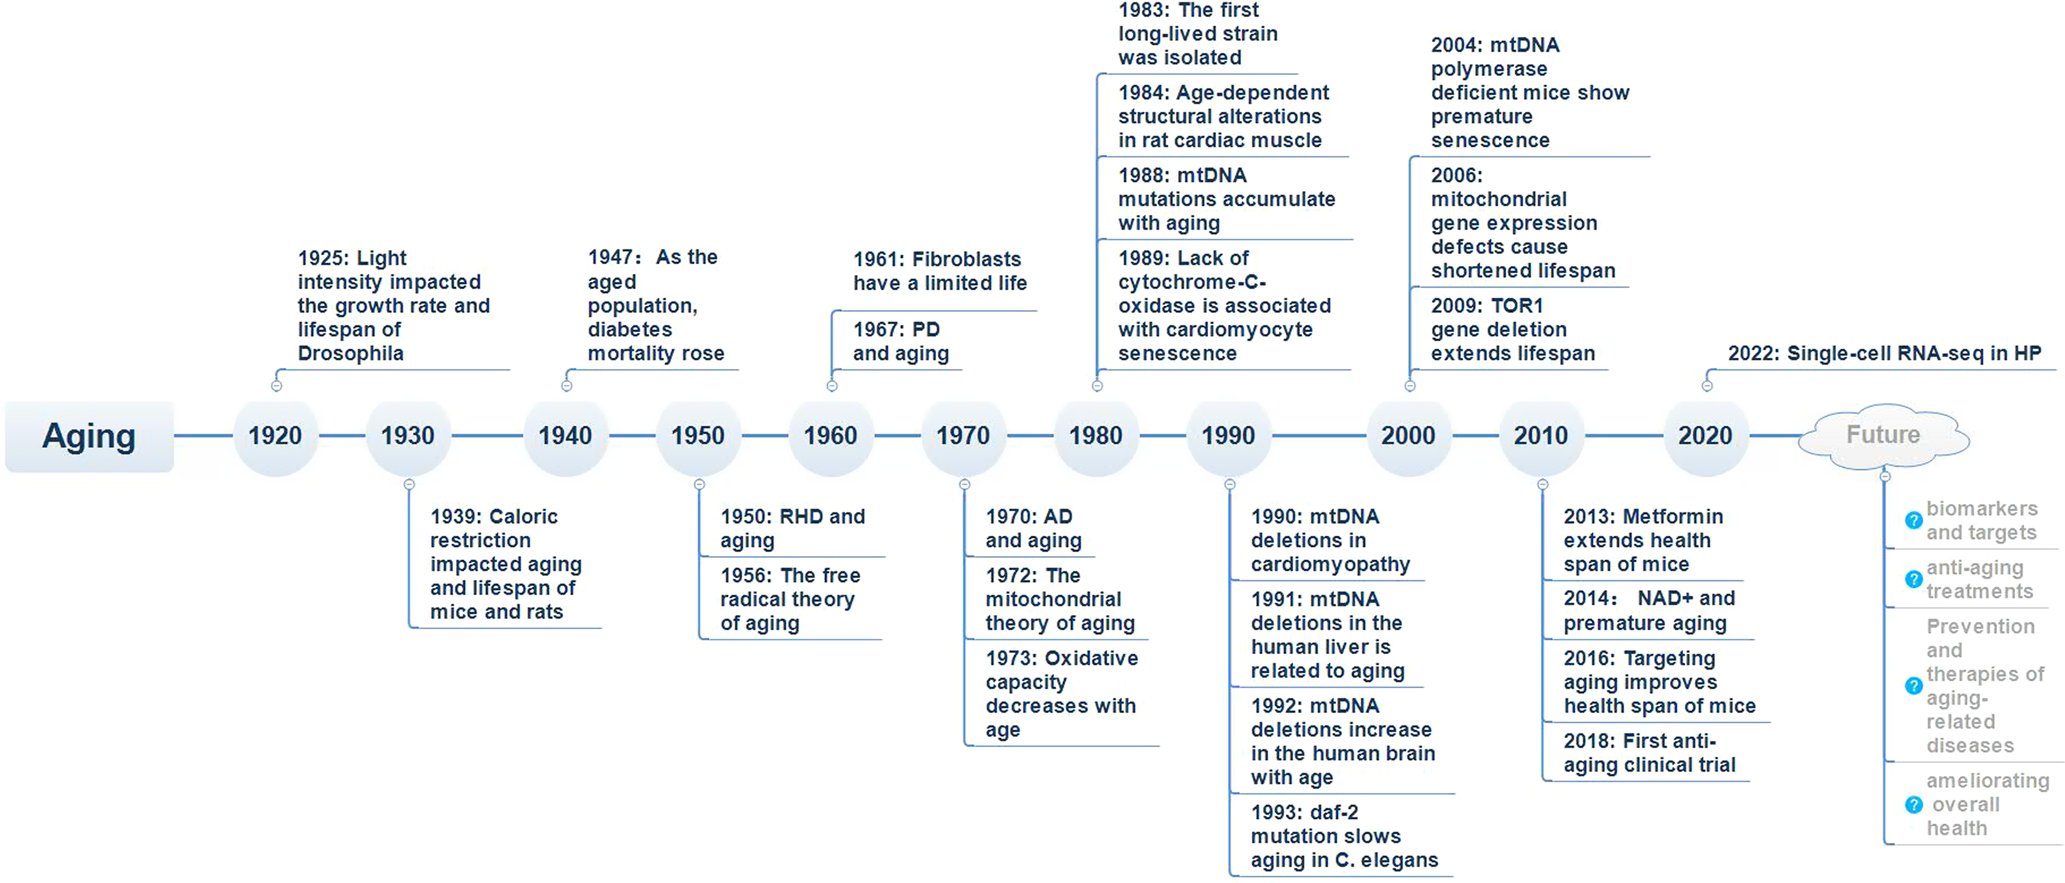

Aging and aging-related diseases: from molecular mechanisms to interventions and treatments nature.com/articles/s4139…